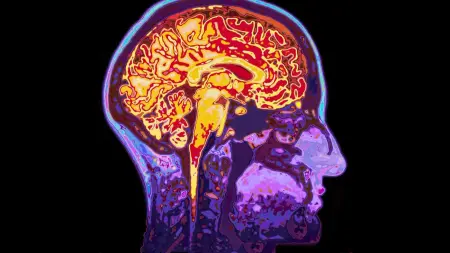

في التجربة، خضع 26 بالغًا للتصوير بالرنين المغناطيسي مرتين: مرة بعد نوم جيد، ومرة بعد ليلة سهر كاملة.

وأظهرت الصور أن التركيز يبدأ بالانخفاض قبل نحو ثانيتين من اندفاع السائل الدماغي إلى الخارج، ثم يعود السائل للتدفّق إلى الداخل بعد استعادة الانتباه بثانية تقريبًا، وكأن الدماغ يجري "غسلة سريعة".